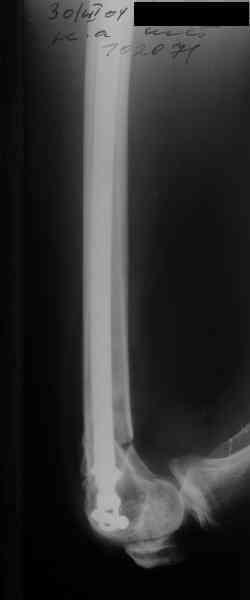

А в чем проблемы? Пример в приложении.

Насчет снимка Вами представленного - смотрится оч красиво, еще бы на функцию узнать...

I> Насчет снимка Вами представленного - смотрится оч красиво, еще бы на

I> функцию узнать...

В приложении функциональные снимки в 3 мес. и в 1 год.